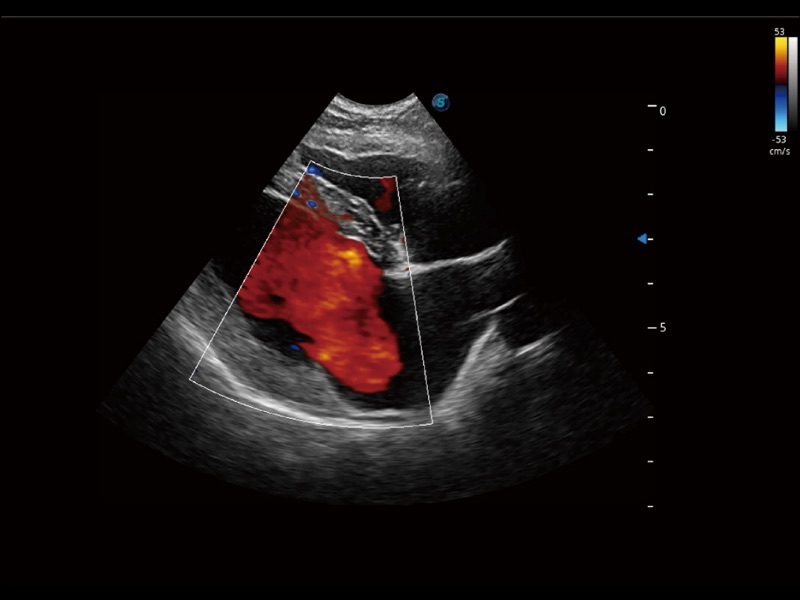

通过创新的 Matrix E自适应滤波器和超长时间域算法,极大提升超低速微细血流的检出能力,同时更精准地滤除软组织和噪声信号,为兽用医生提供以往无法通过常规血流获得的疾病诊断信息。

通过色彩血流和实时宽景相结合,可观察到完整的静脉或动脉的血流,方便医生检查。实时扫查过程中,如有任何操作失误也可以很容易地进行回扫擦除,而不会中断扫查。

实时用颜色表示心肌组织运动,观察和定量组织的运动情况,对快速检测与评估心肌的灌注和活性、电传导及心肌收缩和舒张功能等均能提供重要的诊断信息。